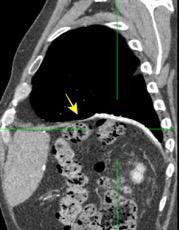

T. mixto de células germinales del testículo

izquierdo Metástasis pulmonares. (flechas verdes). Ganglios paratraqueales. (flechas amarillas). Ganglios retroperitoneales (flechas negras)

Tawfik A et al. Trans-diaphragmatic Pathologies: Anatomical Background and Spread of Disease on cross-sectional Imaging. Current Problems in Diagnostic Radiology. 2021.